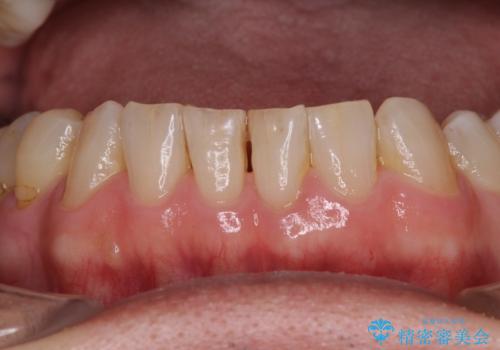

憧れの白い歯に 全顎セラミック治療

- 60歳を越え、黄ばんだ前歯をセラミッククラウンできれいな口元にしたいとのことで来院された患者様です。

健全な歯を削ってセラミッククラウンに置き換えることは、本来避けるべき治療と考えますが、今回は①患者様が60歳を越えていること、②要改善の咬合により抜歯が必要な奥歯があること、③反対咬合の前歯改善の手段としてセラミック治療が選択肢にあることなどから、全顎的なセラミック治療を行うこととしました。